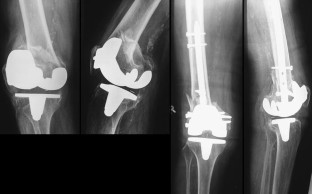

Abb. 5a–c